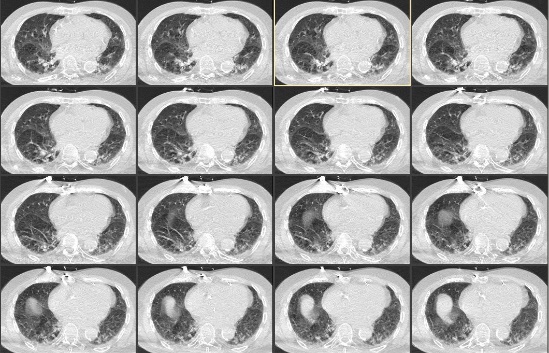

第8天复查肺部CT提示肺部感染(图 2),给予头孢他啶2.0 mg 2次/d抗感染治疗。患者第9天上午9时,患者突发心悸,气急,言语含糊。查体:体温37.3 ℃,脉搏100次/min,血压170/80 mmHg (1 mmHg=0.133 kPa),呼吸25~40次/min,指末氧饱和度SPO2 89%~95%,GCS 2-2-5分,双瞳等大等圆,光敏,双肺呼吸音减低,可闻及少量哮鸣音。血气分析:pH 7.344↓,PCO2 6.76 kPa↑,PO2 6.83 kPa↓,pro-BNP 513.3 pg/mL↑,PCT 0.09 ng/mL;血常规:WBC 9.46×109/L,NEUT% 78.5%↑;血电解质、心肌标志物、心肌酶谱、心超和心动图未见明显异常。经呼吸科和心内科会诊对症治疗后呼吸平稳,血氧饱和度维持95%以上。

| 图 2 患者第8天肺部CT |